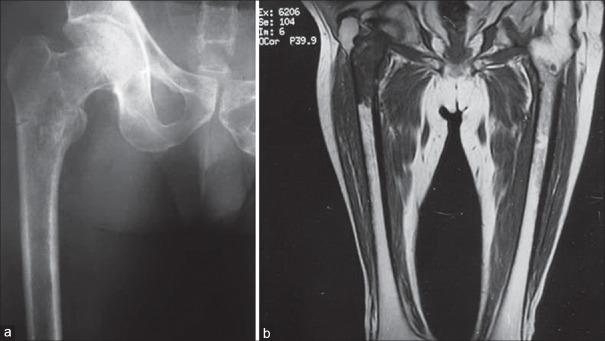

Skeletal metastasis is a common cause of severe morbidity, reduction in quality of life (QOL) and often early mortality. Its prevalence is rising due to a higher rate of diagnosis, better systemic treatment, longer lives with the disease and higher disease burden rate. As people with cancer live longer and with rising sensitivity of body imaging and surveillance, the incidence of pathological fracture, metastatic epidural cord compression is rising and constitutes a challenge for the orthopedic surgeon to maintain their QOL. Metastatic disease is no longer a death sentence condemning patients to "terminal care." In the era of multidisciplinary care and effective systemic targeted and nontargeted therapy, patient expectations of QOL, even during palliative end of care period is high. We lay emphasis on proving the diagnosis of metastasis by biopsy and histopathology and discuss imaging modalities to help estimate fracture risk and map disease extent. This article discusses at length the evidence and decision-making process of various modalities to treat skeletal metastasis. The modalities range from radiation including image-guided, stereotactic and whole body radiation, systemic targeted or hormonal therapy, spinal decompression with or without stabilization, extended curettage with stabilization, resection in select cases with megaprosthetic or biological reconstruction, percutaneous procedures using radio frequency ablation, cementoplasties and discusses the role of emerging modalities like high frequency ultrasound-guided ablation, cryotherapy and whole body radionuclide therapy. The focus lies on the role of multidisciplinary care, which considers complex decisions on patient centric prognosis, comorbidities, cost, feasibility and expectations in order to maximize outcomes on QOL issues.

骨转移是导致严重发病、生活质量(QOL)下降以及常出现早期死亡的常见原因。由于诊断率提高、全身治疗效果更好、患者带病生存时间延长以及疾病负担率上升,其患病率正在上升。随着癌症患者生存期延长以及身体成像和监测的敏感性提高,病理性骨折、转移性硬膜外脊髓压迫的发生率正在上升,这对骨科医生维持患者的生活质量构成了挑战。转移性疾病不再是宣判患者“临终关怀”的死刑判决。在多学科护理以及有效的全身靶向和非靶向治疗时代,即使在姑息性临终关怀阶段,患者对生活质量的期望也很高。我们强调通过活检和组织病理学来证实转移瘤的诊断,并讨论有助于评估骨折风险和描绘疾病范围的成像方式。本文详细讨论了治疗骨转移的各种方式的证据和决策过程。这些方式包括放疗,如影像引导放疗、立体定向放疗和全身放疗、全身靶向或激素治疗、有或无内固定的脊柱减压、扩大刮除术加内固定、在某些病例中进行假体或生物重建的切除术、使用射频消融、骨水泥成形术的经皮手术,并讨论了高频超声引导消融、冷冻疗法和全身放射性核素治疗等新兴方式的作用。重点在于多学科护理的作用,它考虑以患者为中心的预后、合并症、成本、可行性和期望等复杂决策,以最大限度地提高生活质量相关问题的治疗效果。